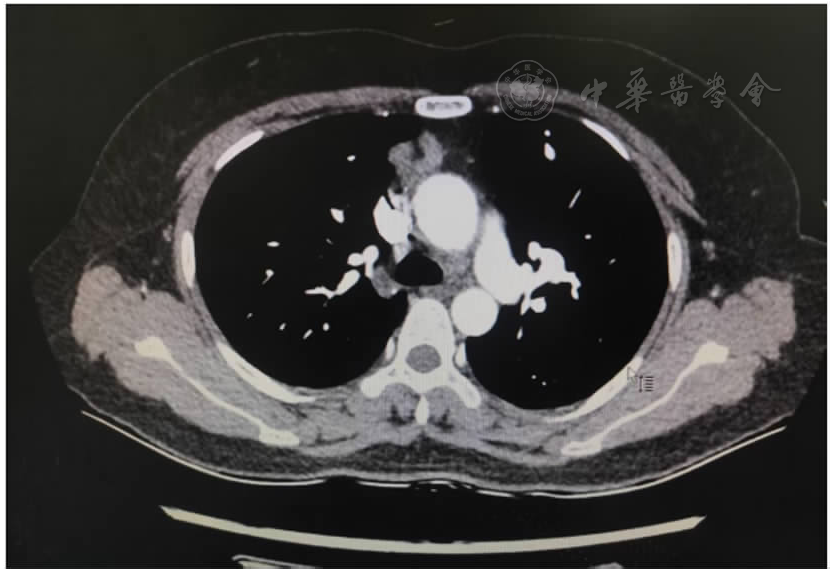

图1 术前CT提示纵隔肿瘤,考虑胸腺瘤可能